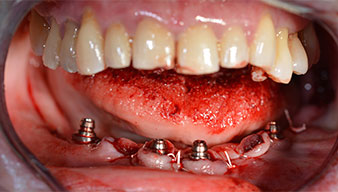

Това кореспондира със следващата зададена програма на Implantmed. Тук виждаме обратния наконечник на W&H под наклон от 45° ъгъл мезиокаодално в областта на 45, с цел да се предпази менталният нерв. Изходът на менталния нерв е използван като анатомична препратка за всички пробивания в тази зона. Следващите отвори са пробити при намалени обороти от 300 rpm (Фиг. 10 и 11).

Ангулираните абатмънти (35°) са завити в имплантите, за да компенсират отклонението от дисталните импланти, така че в резултат профилът на разположение на всички импланти да е възможно най-перпендикулярен на нивото на захапката. Това е предпоставка за оклузално поставяне на временна и впоследствие на постоянна протеза (Фиг. 15 и 16).

Светлината увеличава контраста в оралната кухина и подобрява визуалното възприятие. Обратният наконечник и S-11 прав наконечник на W&H са с външно охлаждане, което е голямо предимство по отношение на физиологичния разтвор, който достига точно, където трябва и може да бъде впоследствие редуциран, ако е необходимо. Правите и обратни наконечници могат да бъдат разглобени, което е силно препоръчително от гледна точка на хигиената и стерилизацията. Поставени са четири импланта SKY с размери 4.0 x 14 мм.